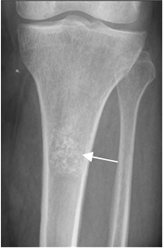

Fig 22. Lesión excéntrica.

Rx AP. Lesión excéntrica en la diáfisis tibial, por defecto fibroso cortical.